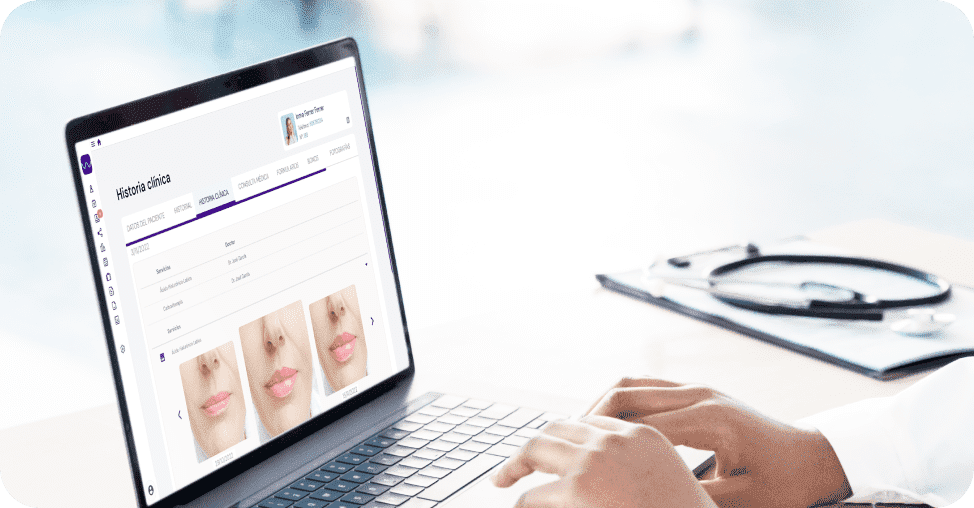

Gestiona fácilmente todos los procesos de tu clínica, apoyándote en herramientas digitales desarrolladas desde la visión del médico, como una completa historia clínica, fotografías y anotaciones de seguimiento, trazabilidad de stock, firma digital y marketing de seguimiento.

Almacena de manera segura la documentación médica del paciente y lleva un control sobre la trazabilidad de consumibles para preservar la seguridad del paciente.